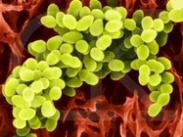

葡萄球菌食物中毒

628健康网为您分享有关葡萄球菌食物中毒的症状,葡萄球菌食物中毒的治疗方法,葡萄球菌食物中毒的预防知识,葡萄球菌食物中...

中毒性休克综合征

628健康网为您分享有关中毒性休克综合征的症状,中毒性休克综合征的治疗方法,中毒性休克综合征的预防知识,中毒性休克综合...